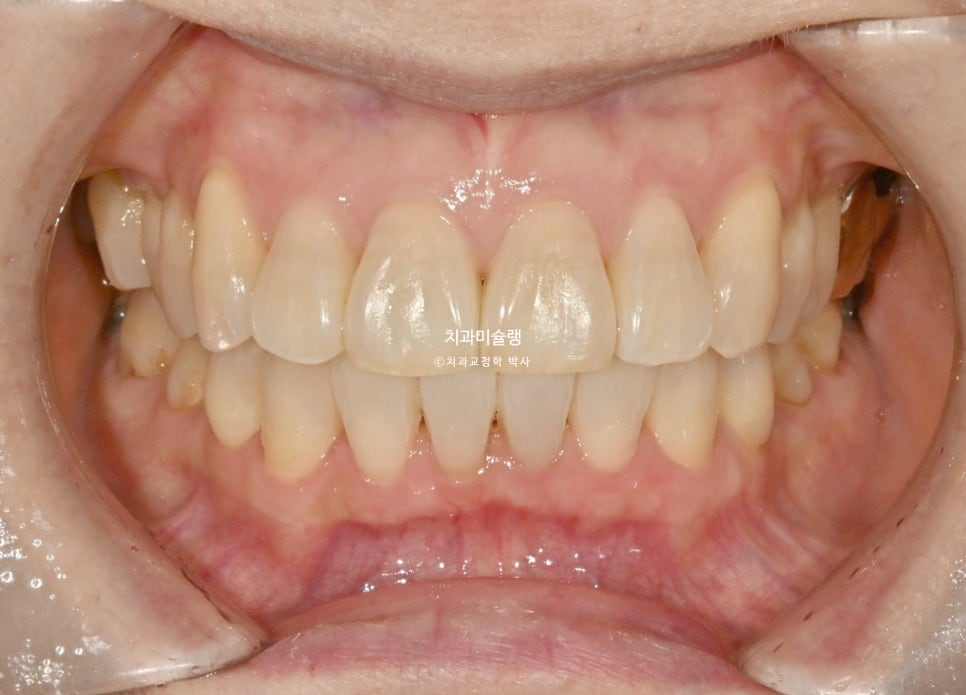

치료 전후 비교

치간삭제를 통해 블랙트라이앵글은 많이 줄었으며

앞니 뻗침도 소량 개선되었습니다.

앞니가 정돈되니 한결 깔끔해진 미소가 눈에 띕니다.

앞니 돌출 해소로 입술부전증이 해소되어 턱끝에 힘이 풀리며 호두턱(자갈턱)이 없어졌습니다.

돌출된 위 앞니가 뒤로 들어가며 아랫입술이 편하게 물립니다.